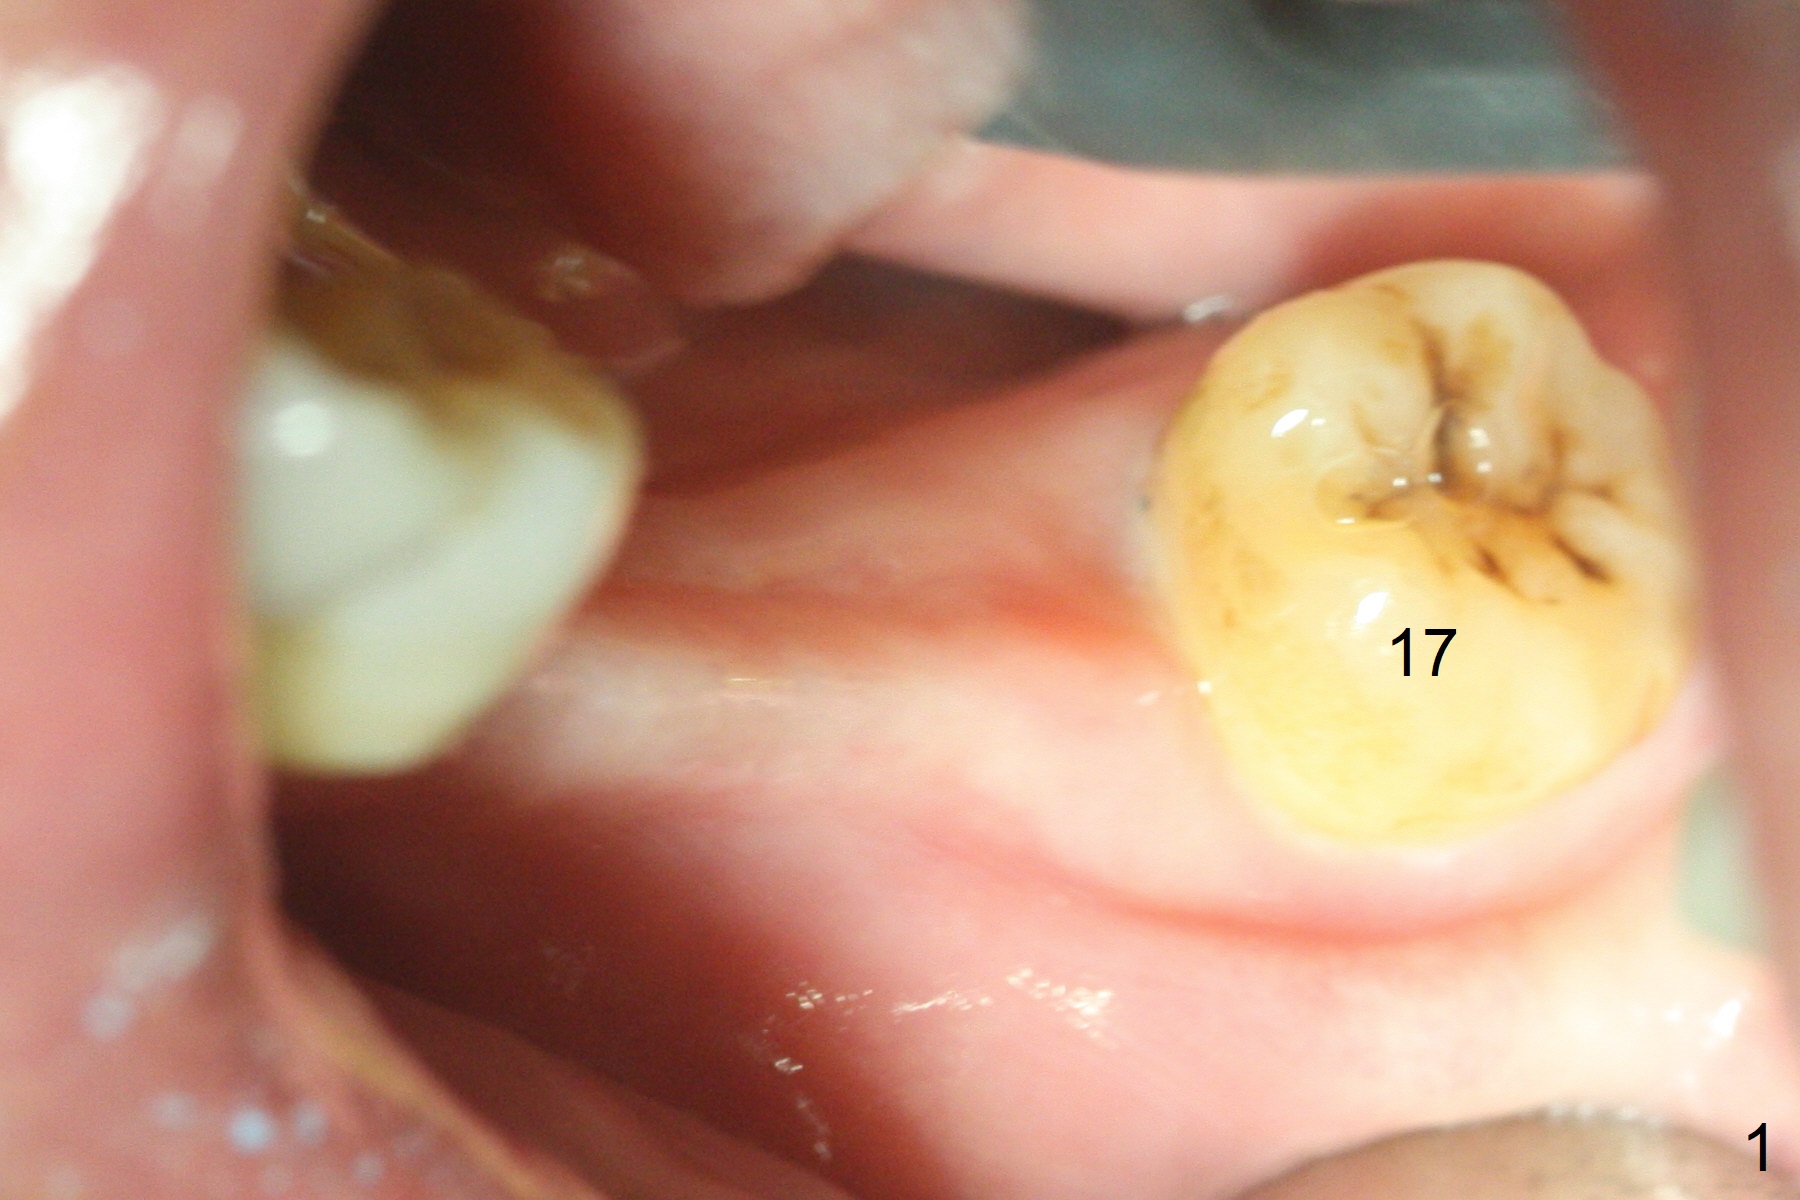

Preop photo confirms the lower left posterior pointed ridge (Fig.1). After ridge reduction and 2 mm drill for 8 mm, a parallel pin is inserted (Fig.2). A 3.8x8 mm SM implant is placed with >50 Ncm (Fig.3). The coronal threads (buccodistal) is covered with VeraGraft after placement of 4.1x5(3) mm healing abutment. The tooth #17 is not planned for extraction while the implant is osteointegrated. The tooth appears to be too loose and is extracted ~ 1.5 months postop. The implant seems to be osteointegrated 3 months postop (Fig.4). The healing abutment is changed to ball abutments with 4 mm (Fig.5) and 2 mm (Fig.6) cuffs. In fact the latter stays. What is the special device at the site of #18 (ring, Fig.7 <)?